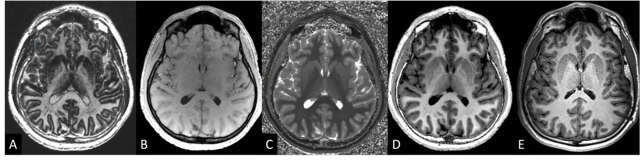

Les méthodes d'imagerie basées sur la TEP permettraient d'obtenir des mesures de la f

raction d'éjection ventriculaire gauche comparables à celles obtenues par IRM cardiaque (

étude).